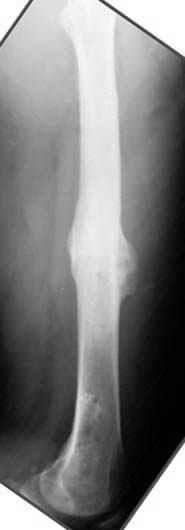

Несколько снимков из моей коллекции, чтобы разьяснить, почему мы до сих пор делаем различные варианты остеотомии.

На рисунке N1 предоперационный план лечения ложного сустава шейки бедра- линия ложного сустава, угол и направление введения импланта, клиновидная остеотомия в градусах и миллиметрах, второй снимок после коррекции, расчет, на сколько удлиняется конечность и размеры импланта;

N3 рисунок окончательный снимок, после операции моя рентгенограмма должен выглядеть примерно как эта картина. На N4 снимке клин перед удалением; N5 послеоперации 3 нед.; N6 окончательная рентгенограмма.

Отправитель: Djoldas Kuldjanov 23 Ноябрь 2004, 18:21

пластическая модель; и коррекция бедра аппаратом Илизарова.